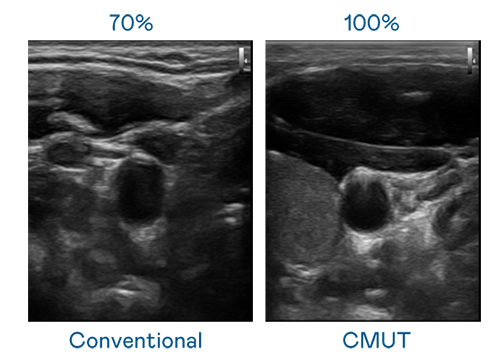

CMUT 技术是一种用电容式微机电元件来产生超音波讯号的技术。与传统 PZT 压电式技术相比,CMUT 频宽增加 30%,更宽频的超音波讯号让影像解析度大幅提升,是实现高影像品质医疗超音波扫描、促进精准医疗发展的关键技术。

大频宽带来超清晰影像

超音波影像的解析度高低,首先取决于探头能发出的讯号频宽。sungame CMUT 可提供高清晰的超音波讯号,提供高频宽、高灵敏度、影像纹理细节更高的超音波影像,协助医护人员缩短影像判读时间及利用精准的医疗影像进行诊断。